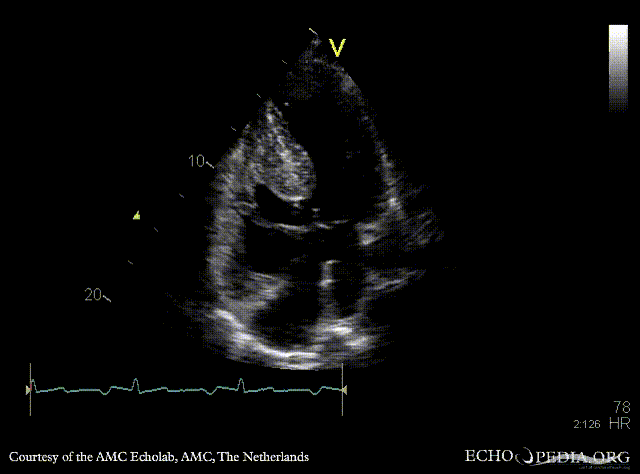

| PLAX: AVSD